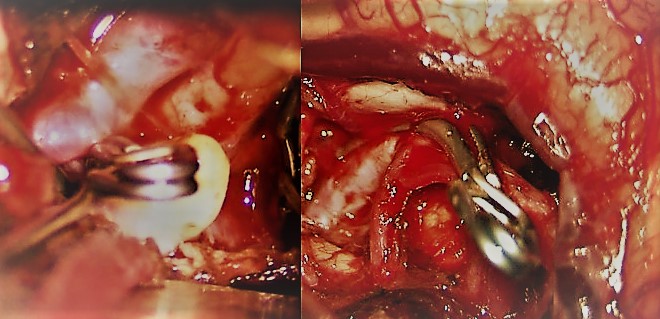

- Aneurismas cerebrales: Representan la causa más frecuente de hemorragia subaracnoidea espontánea (75-80% de los casos). Se trata de dilataciones de las arterias debidas a la debilidad en la pared de las mismas. Ello provoca que pueda tener lugar la ruptura de la arteria con la consiguiente hemorragia. La frecuencia de aneurismas cerebrales en la población se sitúa en torno a un 1-5%. En caso de ser diagnosticados inmediantamente tras una hemorragia subaracnoidea deben ser tratados tan pronto como sea posible para minimizar el riesgo de resangrado. En otras ocasiones tiene lugar el diagnóstico de aneurisma cerebral en pacientes asintomáticos sin que se haya producido la ruptura del mismo. En estos casos ha de valorarse la posibilidad de tratar el aneurisma de forma preventiva para evitar que en un futuro tenga lugar la hemorragia subaracnoidea. Tanto en un caso como en otro, el tratamiento puede llevarse a cabo de forma endovascular, mediante cateterismo cerebral, o bien mediante cirugía la cual permite el clipaje y cierre definitivo del aneurisma. La decisión sobre el tratamiento y la elección de una técnica u otra va a depender fundamentalmente de la localización del aneurisma, sus relaciones anatómicas con las ramas arteriales afectadas, el tamaño de mismo, la edad y condición clínica de cada paciente.

- Malformaciones arteriovenosas (MAV): Responsables de un 4-5% de las hemorragias subaracnoideas. Están representadas fundamentalmente por las MAV piales, caracterizadas por la presencia de ramas arteriales que dan lugar a un nido malformativo, compuesto por arteriolas y capilares aberrantes, que recibe sangre a alta presión y que drena a través de una o varias venas. Por lo general, se trata de lesiones complejas cuyo tratamiento va a estar condicionado por su tamaño, localización dentro del cerebro y características del drenaje venoso. En caso de que se diagnostiquen previo a su ruptura (generalmente debido a que pueden inducir crisis epilépticas) y midan menos de 3 centímetros, pueden ser tratadas con radiocirugía, si bien en estos casos el efecto del tratamiento se demora unos 2 años. La cirugía por su parte constituye el tratamiento estándar de estas lesiones. Puede tener lugar, al igual que los aneurismas, de forma previa a la ruptura o bien tras producirse ésta. Previo a la cirugía debe considerarse la posibilidad de la embolización de la lesión.